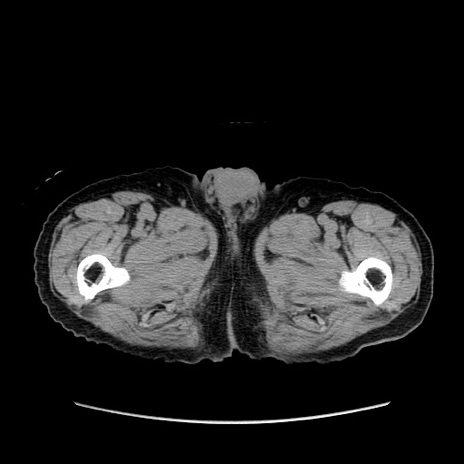

症例24(横断像)

【症例】80歳代男性

【主訴】左側腹部痛、嘔吐

【現病歴】本日早朝より左腹部に痛みあり。昼頃嘔吐認めたため、救急要請。

【既往歴】直腸癌(Mile手術)、胆摘

【身体所見】意識清明、BT 35.9℃、BP 221/93mmHg、SpO2 97%(RA) 、腹部:左ストーマ周囲に限局性の腹部膨隆あり。 膨隆部自発痛・圧痛あり・軟。

【データ】WBC 7700、CRP 0.09